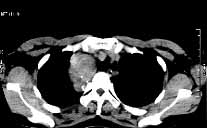

甲狀腺癌的診斷只根據臨床表現不能確定應綜合評價才能明確診斷。甲狀腺腫塊生長較速,有轉移灶,且有明顯壓迫症狀甲狀腺功能減退,甲狀腺掃描多冷結節,或發現甲狀腺CT掃描及MRI影像有異常及轉移現象,最後診斷應根據病理活檢,明確為甲狀腺乳頭狀癌濾泡癌、未分化癌或混合性癌等。

2.CT和MRI 不但能查甲狀腺腫瘤的大小,還能了解浸潤周圍組織的情況、腫塊與喉結、食管、氣管的關係淋巴結有無轉移。圖像清楚、準確率高